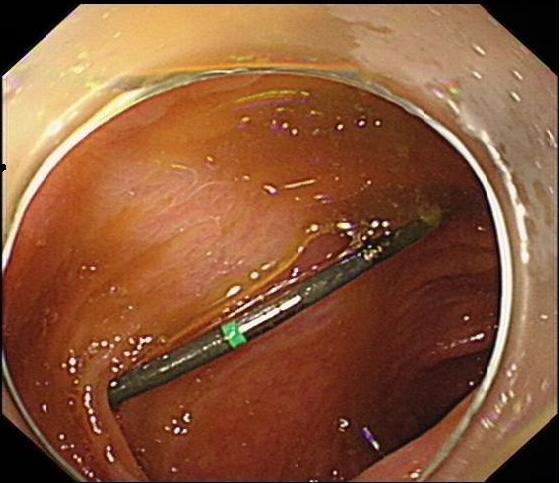

2.2 术前准备及术中配合根据无痛胃肠镜要求,对患者进行肠道准备及禁食禁饮宣教,护士加强患者心理支持,并做好仪器设备准备,如抢救车、除颤仪等。结肠镜前端置透明帽后循腔进镜,经直肠、乙状结肠、降结肠、横结肠时,见1个条形金属异物,长约3 cm(图 7),观察到一端已插入肠壁,首先选用异物钳将插入尖锐端金属轻轻拔出。为避免金属钻易脱落,强行取出异物容易造成肠道二次损伤,改用圈套器将尖锐端套住收紧后拉入透明帽内配合医生不断变换角度,调整方向,使异物方向和镜身尽量保持平行(图 8)缓慢通过各结肠弯曲部,顺利将异物取出(图 9)。整个内镜操作过程只用了15 min,无出血和穿孔等并发症发生。

| 图 7 通过横结肠,可见尖锐异物 |

| 图 8 圈套器将尖锐端套住收紧后拉入透明帽内,调整方向,使异物方向使镜身尽量保持平行,缓慢通过各结肠弯曲部 |